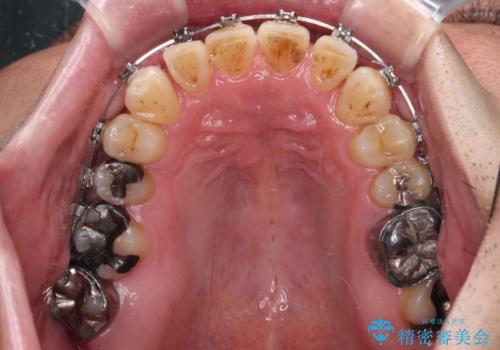

- 矯正装置

- メタルブラケット

- 治療期間

- 3年1ヶ月

- 治療回数

- 30回以上